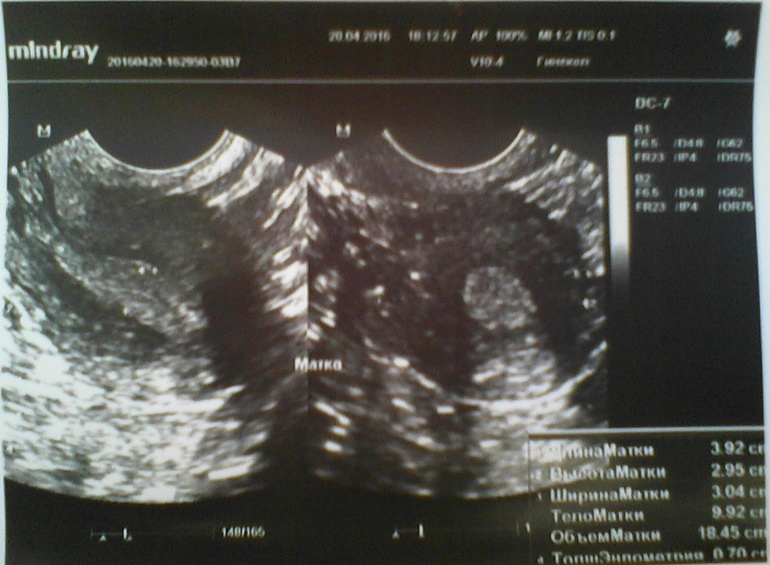

Сегодня 15ДЦ, решила сходить на УЗИ, проверить как-там мои фолики в этом цикле и опять ..........ДФ нет!!!!! Уже третий цикл подряд я без О!!!Получается, что этот цикл пролётный, в следующем только сдам гормоны и только потом, на 3 цикл мне уже хоть что-нибудь назначат(((((К слову БТ высокая в первой фазе, средняя 36,8!Последние два цикла были 20 и 25 дней....посмотрим, что будет на этот раз!

Результаты УЗИ прилагаю!